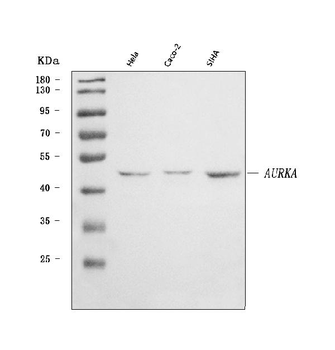

50 μl, 100 μl, 200 μlAnti-Aurora A/AURKA Antibody [orb1290027]

ELISA, FC, IHC, WB

Human

Rabbit

Polyclonal

Unconjugated

10 μg, 100 μgChemerin Rabbit Polyclonal Antibody [orb156351]